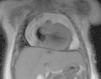

Ante la negatividad de los estudios microbiológicos y con sospecha de probable etiología metabólica por detección de hipocarnitinemia, se añadió carnitina al tratamiento (100mg/kg/d) a las 48h y un día después glucocorticoides e inmunoglobulinas. En el examen anatomopatológico del líquido pericárdico, se dudó sobre la existencia de células tumorales. Se realizó RNM, que no evidenció ninguna masa tumoral (fig. 2).